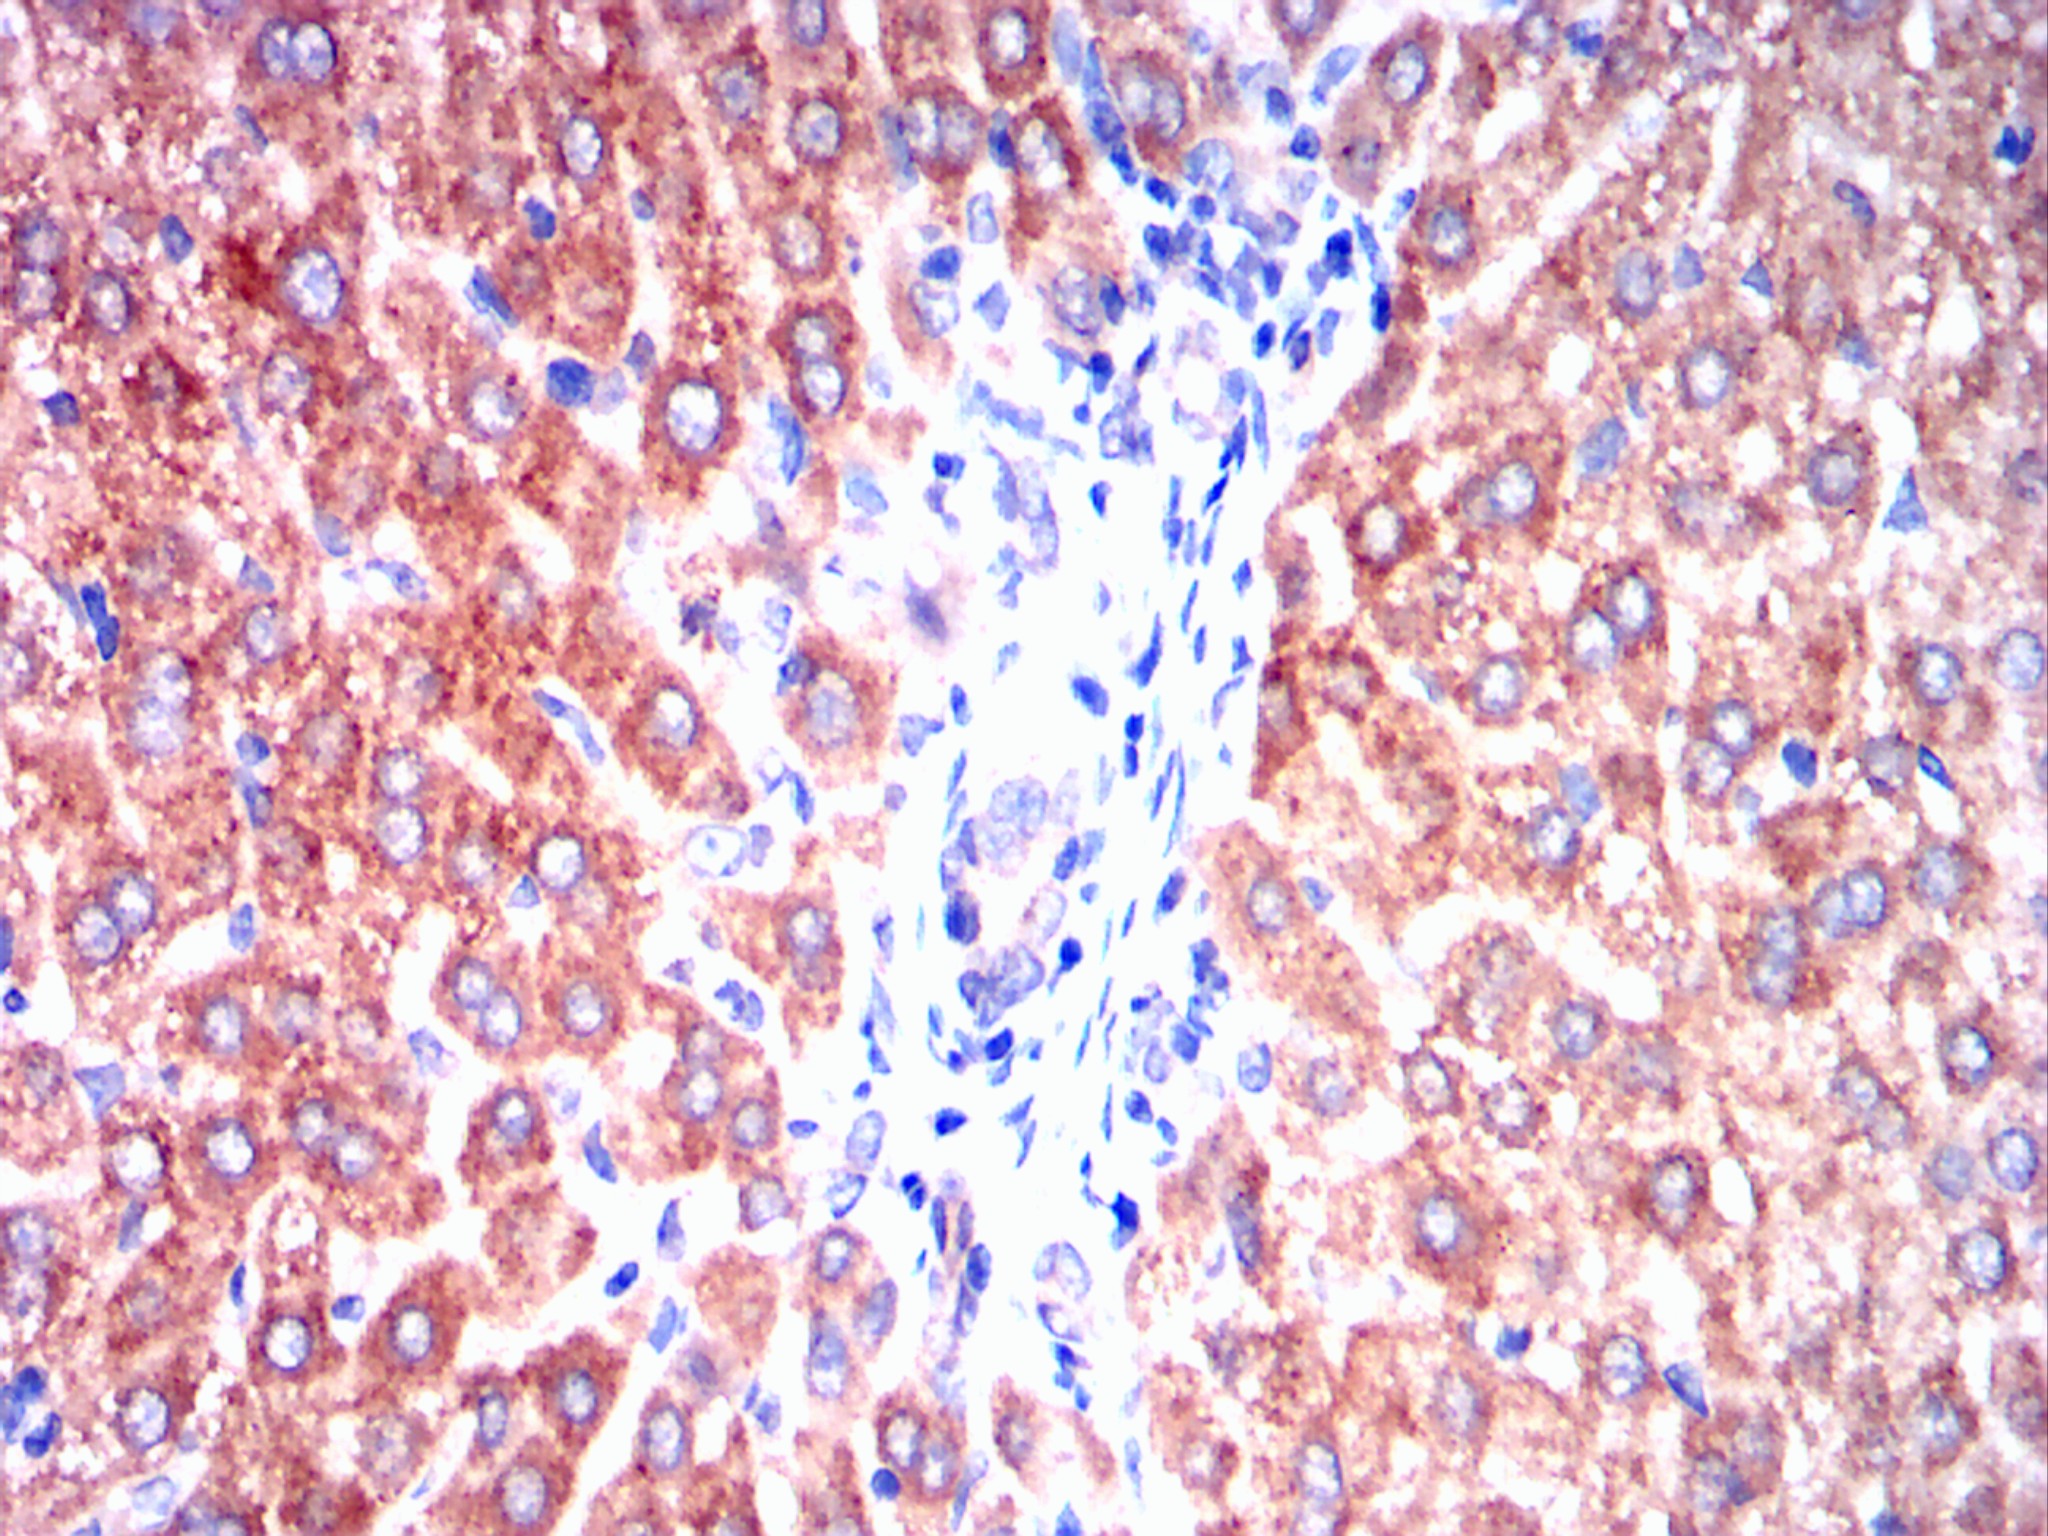

Immunohistochemical analysis of paraffin-embedded rabbit kidney tissues using ERBB3 mouse mAb with DAB staining.

Immunohistochemical analysis of paraffin-embedded rabbit liver tissues using ERBB3 mouse mAb with DAB staining.